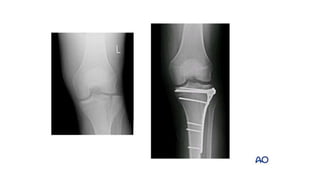

Condylar plates • Theseare special type of implants • It is most commonly used in periarticular fractures , wherein it maintains the anatomical reduction as well as fixes the metaphyseal fragments to the diaphysis. • Eg 95 degree dcp is used in the management of distal femur fractures, proximal femur comminuted fractures, osteotomies of proximal femur, etc.